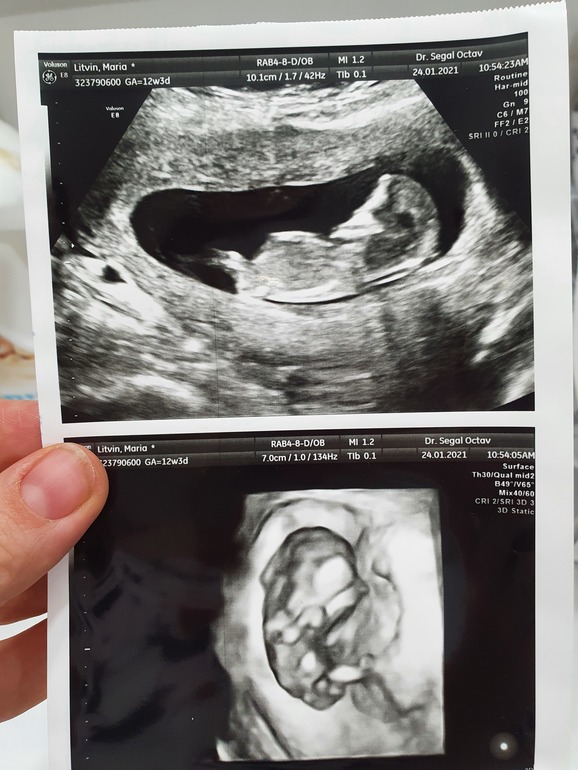

Девочки, у кого глаз-алмаз? Мальчик/девочка? Через месяц идем на узи, пока только такая фотка)))😍 12+4

Если я верно разглядела и это оно, то я больше к парню склоняюсь. Но видно плохо, точнее практически ничего не видно

В 3D непонятно ничего. В обычном - не видно: там ножка закрыла половой бугорок.

На таком сроке пол в таком ракурсе не смотрят, в 12 недель у мальчиков и девочек между ножек все одинаковое, половые органы ещё не сформированы и есть только половой бугорок. Пол предполагают по его наклону - у мальчиков вверх торчит, у девочек параллелен позвоночнику. Поэтому смотрят, когда малыш лежит четко в профиль.

Masha_Lit, на нем ракурс хороший, но полового бугорка не видно. То ли ножка закрывает, то ли пуповина. Сходите на УЗИ в 16 недель, в 16 уже скажут точно пол,если малыш не закроется.